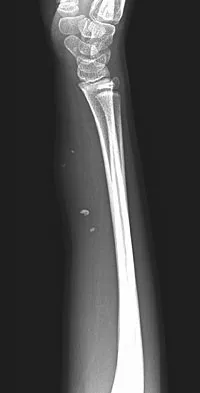

A 57-year-old man has had right ankle pain for the past 10 months following an injury that went untreated. Radiographs are shown in Figures 30a through 30c. Management should consist of

Explanation

The radiographs reveal a malunited distal fibular fracture with shortening. Because there appears to be an adequate cartilage space within the ankle joint, the role of reconstruction would be to prevent arthrosis and the need for ankle arthrodesis, as well as to decrease symptoms. The treatment of choice is restoration of fibular length, alignment, and rotation with osteotomy plating, and bone grafting as needed. There is no indication for ligament reconstruction of a mechanically stable ankle, and tibial shortening osteotomy will not assist in correcting the deformity. Cast immobilization may assist with improvement of symptoms but will not correct the overall process. Determination of fibular length is best done by comparing the talocrural angle of the injured side with the uninjured side. The goal is to perfectly reduce the talus in the ankle mortise. Marti RK, Raaymakers EL, Nolte PA: Malunited ankle fractures: The late results of reconstruction. J Bone Joint Surg Br 1990;72:709-713. Geissler W, Tsao A, Hughes J: Fractures and injuries of the ankle, in Rockwood CA Jr, Green DP, Bucholz RW, Heckman JD (eds): Rockwood and Green's Fractures in Adults, ed 4. Philadelphia, PA, Lippincott-Raven, 1996, pp 2201-2206.